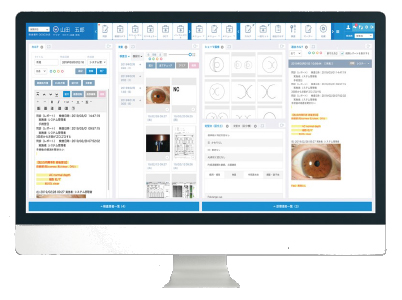

Medius CL

電子カルテシステム

主な特徴

・院内に今、何人患者がいるか各セッションの混雑状態などスタッフ全員で情報共有が可能です。スタッフ間で共有がすぐにできるのできめ細かい接遇につながります。

・足が悪い、耳が遠いなどの対応が必要な患者情報をスタッフ全員で共有でき事故を防止できます。患者様の情報共有がもれなくできるのは安心なシステムです。

・Do機能により問診・検査・診察所見・処方に引用記載ができるので入力時間の短縮が可能となり待ち時間の短縮ができます。患者様の待ち時間の短縮につながります。